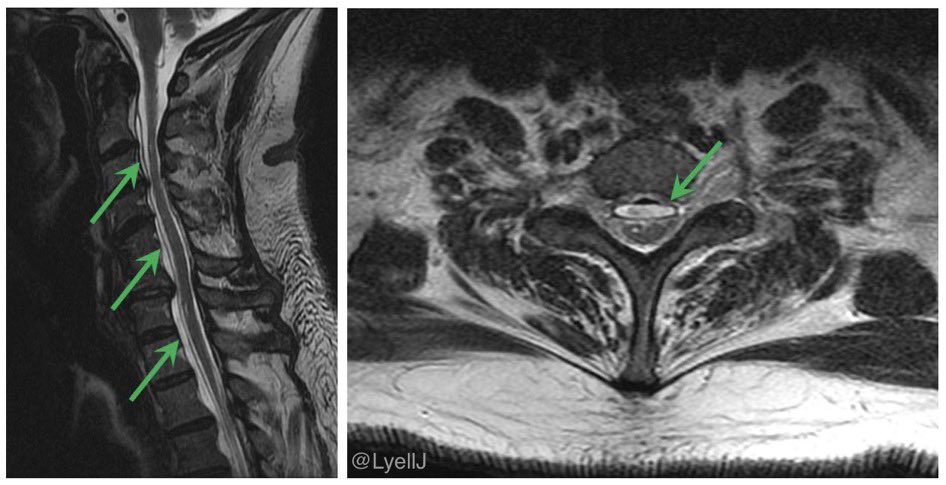

A 61 year old man comes in for another opinion on his diagnosis of ALS

Several years of progressive upper limb weakness

Exam: upper limb fasciculations, brisk lower limb reflexes

One look at the C-spine MR and you know it’s not ALS. What’s going on? Image The imaging demonstrates a spinal longitudinal extradural CSF collection (SLEC)

➡️ Indicates a dural tear (usually ventral) and a fast CSF leak

There are relatively few mimics of ALS, and bibrachial amyotrophy from a CSF leak is one not to be missed Image